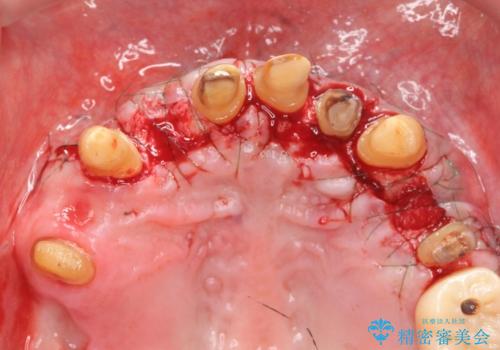

セラミック治療を行う前に歯周病の問題を解決すべく歯周外科を行い歯周ポケットを除去し整備したのちセラミックブリッジ・クラウンの製作を行います。

歯周外科を行ったことで非常に安定した歯周環境となり、引き締まった歯ぐきとなりました。